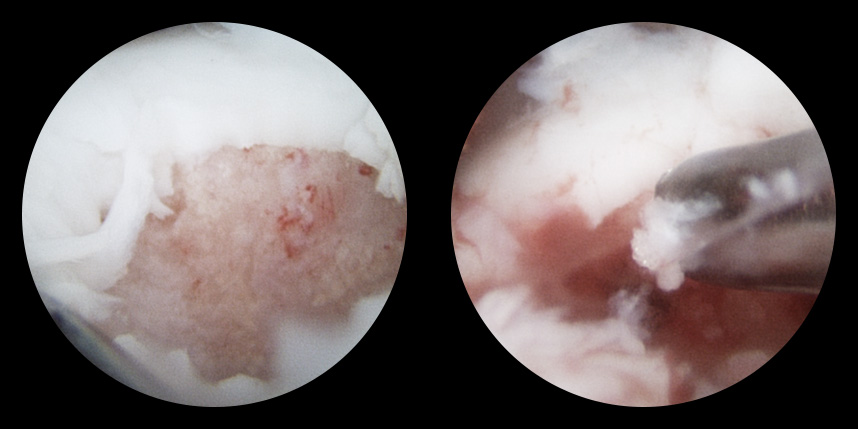

손상된 연골 부위에 작은 구멍을 뚫어 골수에서 나오는 줄기세포를 이용하여 연골 재생을 유도하는 방법으로 근본적으로 섬유연골(정상연골보다는 약한 연골)로 재생된다고 알려져 있습니다.

특수하게 농축하여 제작된 6% 콜라겐(리젠실603) 또는 9% 콜라겐(이엔카티)을 천공술을 시행한 부위에 덮어 주어 미세천공술 단독보다 좋은 치료 결과를 기대할 수 있습니다.

본원에서는 미세천공술, 콜라겐주입술, 카티스템 치료를 주로 하고 있습니다.

연골 손상이 크거나 작고 어느 위치에 있어도 연골재생술이 가능합니다.

전통적으로 증명이 된 미세천공술을 항상 같이 시행